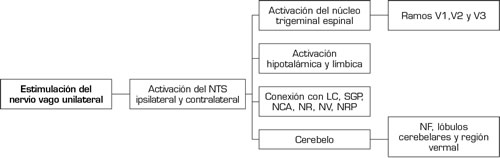

De manera clásica se ha considerado que el papel de la EVNI está relacionado con la modulación del reflejo trigeminal autonómico disminuyendo su componente parasimpático. En el nuevo entendimiento de las interacciones neuroanatómicas del sistema trigémino-vagal, un estímulo a nivel cervical sobre el NX de manera unilateral tiene la capacidad de generar activación bilateral a nivel del núcleo del tracto solitario, el núcleo parabraquial con una comunicación directa hacia el hipocampo (4,5). De manera adicional, el estudio de Henssen y cols. (6) propone la comunicación con los núcleos del rafe, los núcleos vermales y fastigiales a nivel cerebelar y el locus coeruleus. Estas estructuras están implicadas directamente en la modulación del dolor debido a su interacción con la sustancia gris periacueductal y la activación de las vías GABAérgicas y serotoninérgicas (7) (Figura 2).

NTS: núcleo del tracto solitario. LC: locus coeruleus. SGP: sustancia gris periacueductal. NCA: núcleo central de la amígdala. NF: núcleo fastigial. NR: núcleos del rafe pálido y oscuro. NV: núcleo vestibular. NRP: núcleo reticular parvocelular.

Fig. 2. Sistema trigémino-vagal.